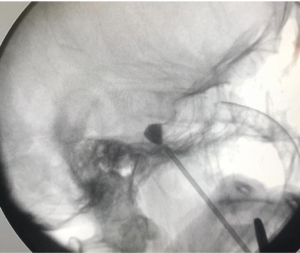

Na figura abaixo temos um exemplo de como é a cirurgia de neuralgia do trigêmeo, neste caso, realizando a compressão do gânglio trigeminal por balão. Neste procedimento, uma cânula é inserida através da face e por dentro dela, passa-se um balão que é insuflado no cavum de Meckel.

Observe o formato do balão, em “pêra”, que denota um posicionamento ideal.

Compressão percutânea por balão do nervo trigêmeo guiada por fluoroscopia, técnica minimamente invasiva utilizada no tratamento da neuralgia do trigêmeo.

Imagem fluoroscópica durante compressão percutânea por balão do nervo trigêmeo, procedimento minimamente invasivo utilizado no tratamento da neuralgia do trigêmeo.

Exemplo de uma compressão do gânglio trigeminal por balão. Com uma cânula que passa através do forame oval, o cavum trigeminal é acessado. Por dentro da cânula, é passado um cateter de Fogarty 4F, que é insuflado (geralmente por 60 segundos), gerando uma lesão mecânica no gânglio / raíz trigeminal.